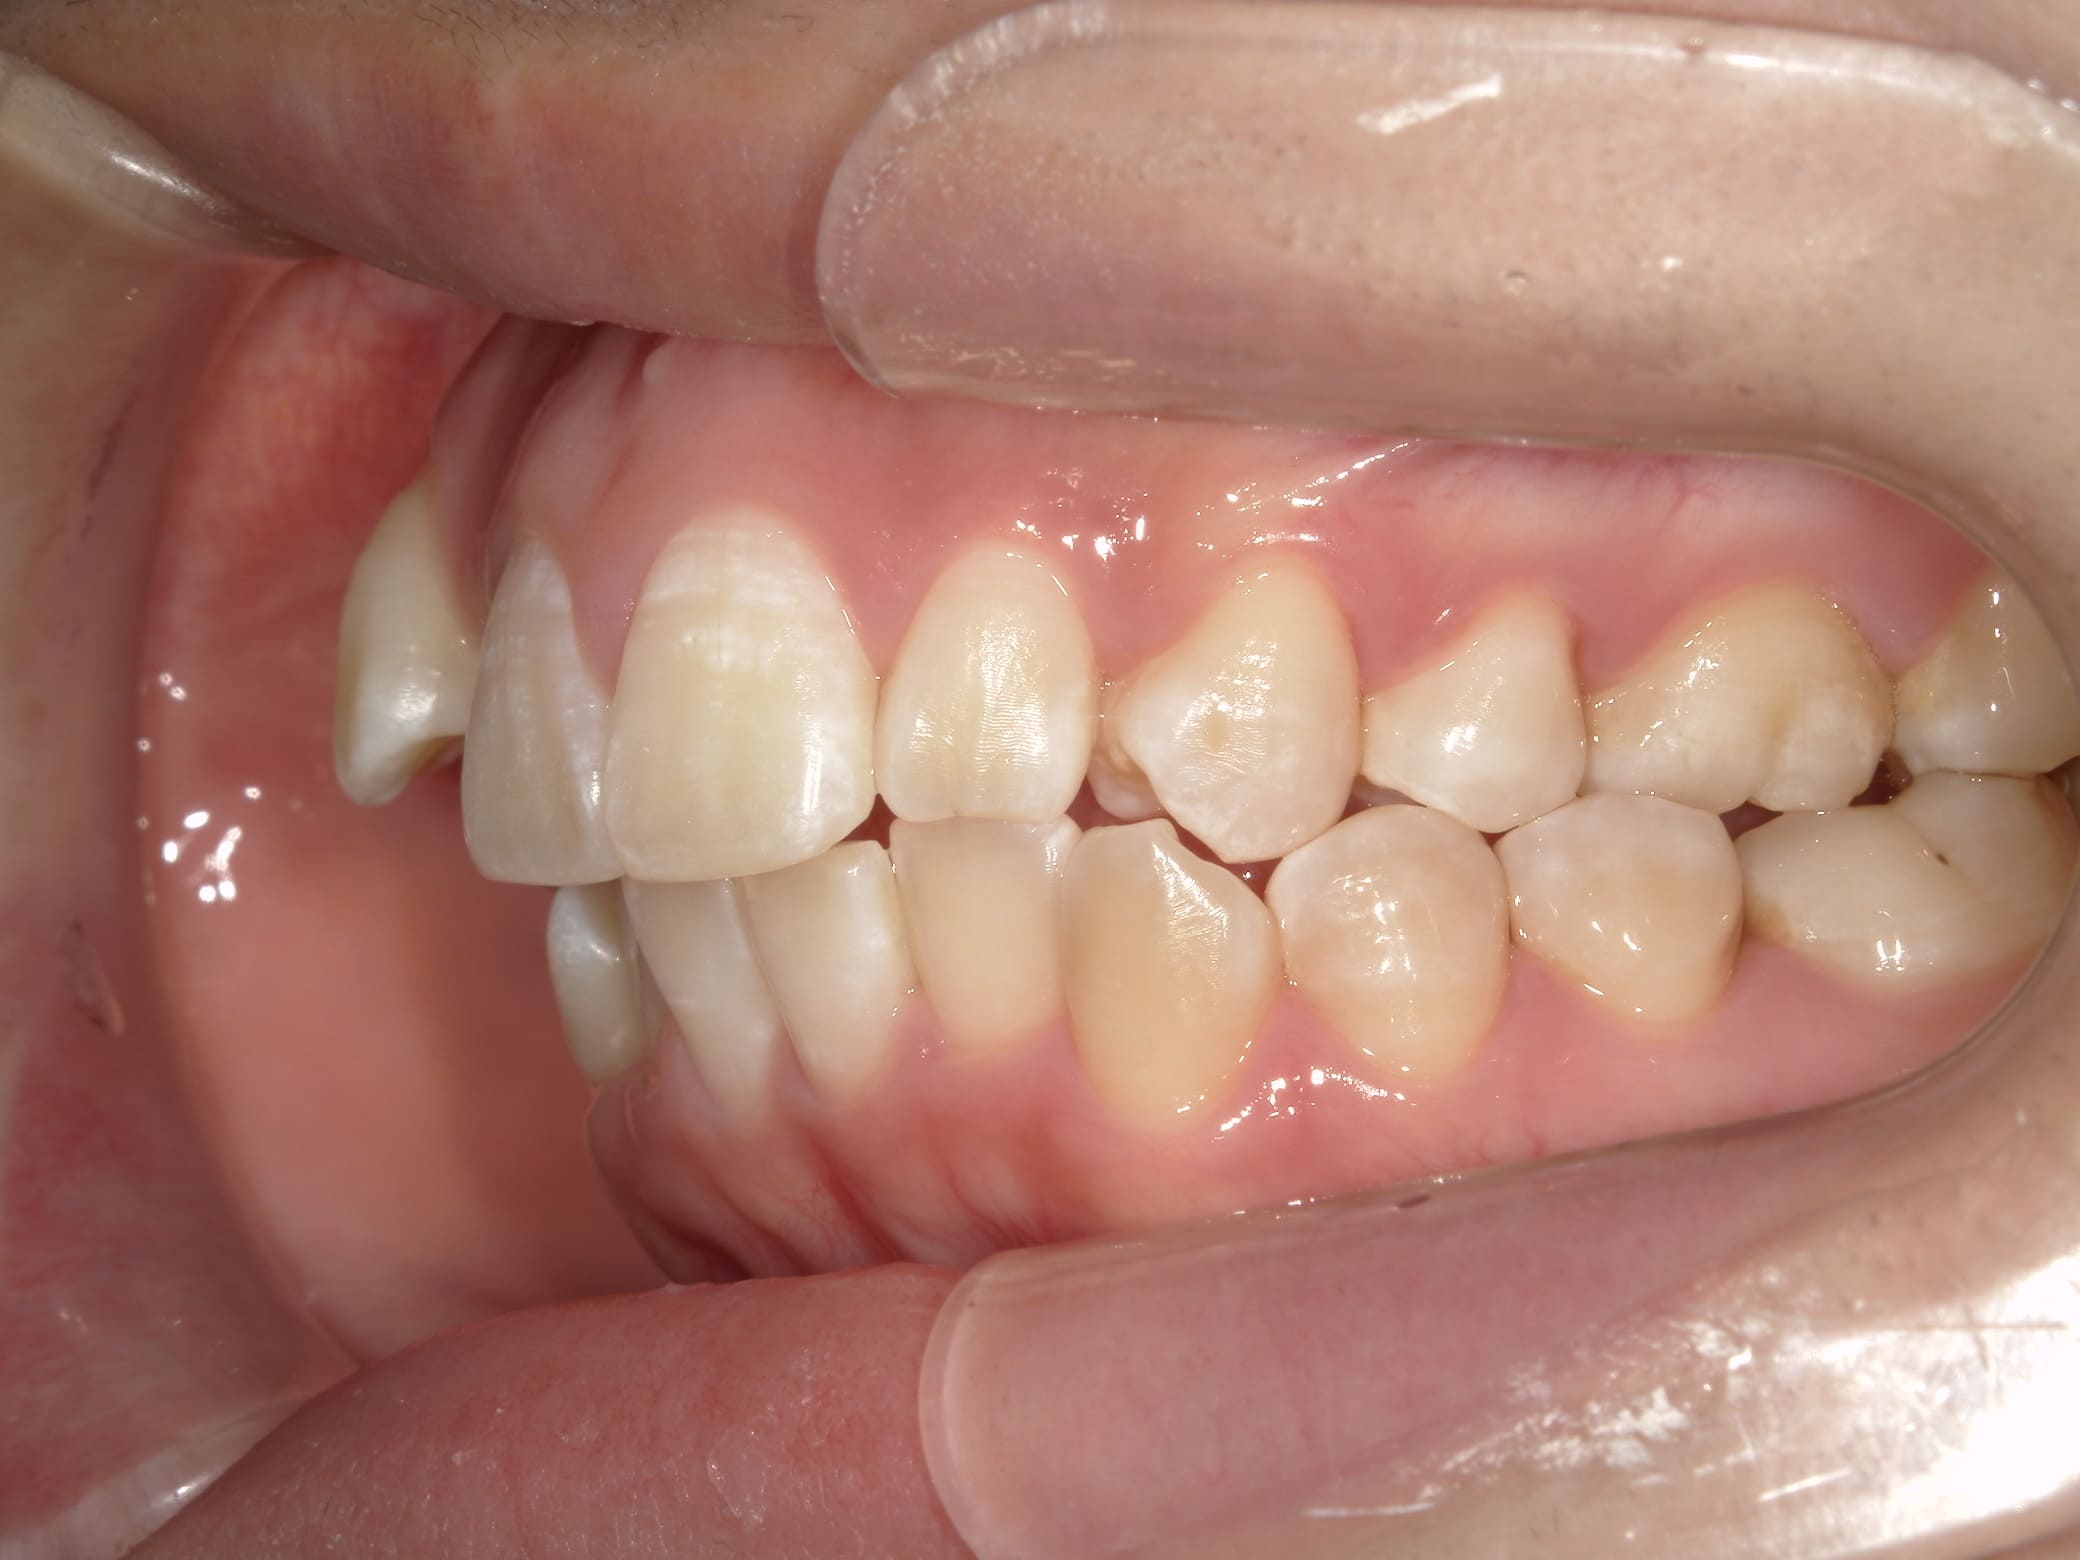

| 年齢・性別 | – |

|---|---|

| 主訴 | 叢生が気になる |

| 治療期間・回数 | 1年9ヶ月 |

| 費用 | 1,011,000円 |